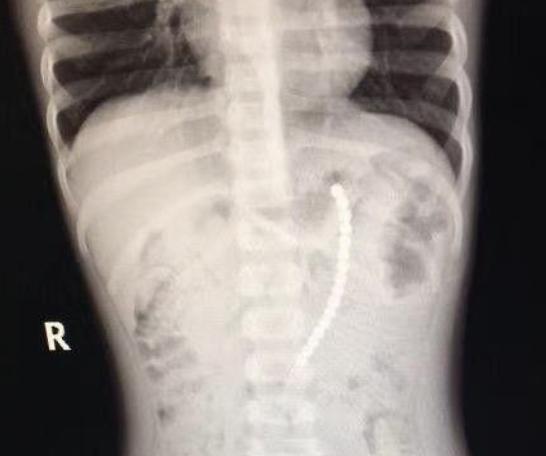

天不绝我,我在某点看爽文时,居然看见整整一章描写孩子如何误吞磁力珠,带磁力的小球在体内肠道、胃里的不同位置紧紧吸附,导致胃穿孔肠梗阻。开挂男主大发神威,取出“珍珠项链一样”(比喻实在太生动,记得太清楚了)的一串珠子,瞬间挽救狂澜。

图片来自网络